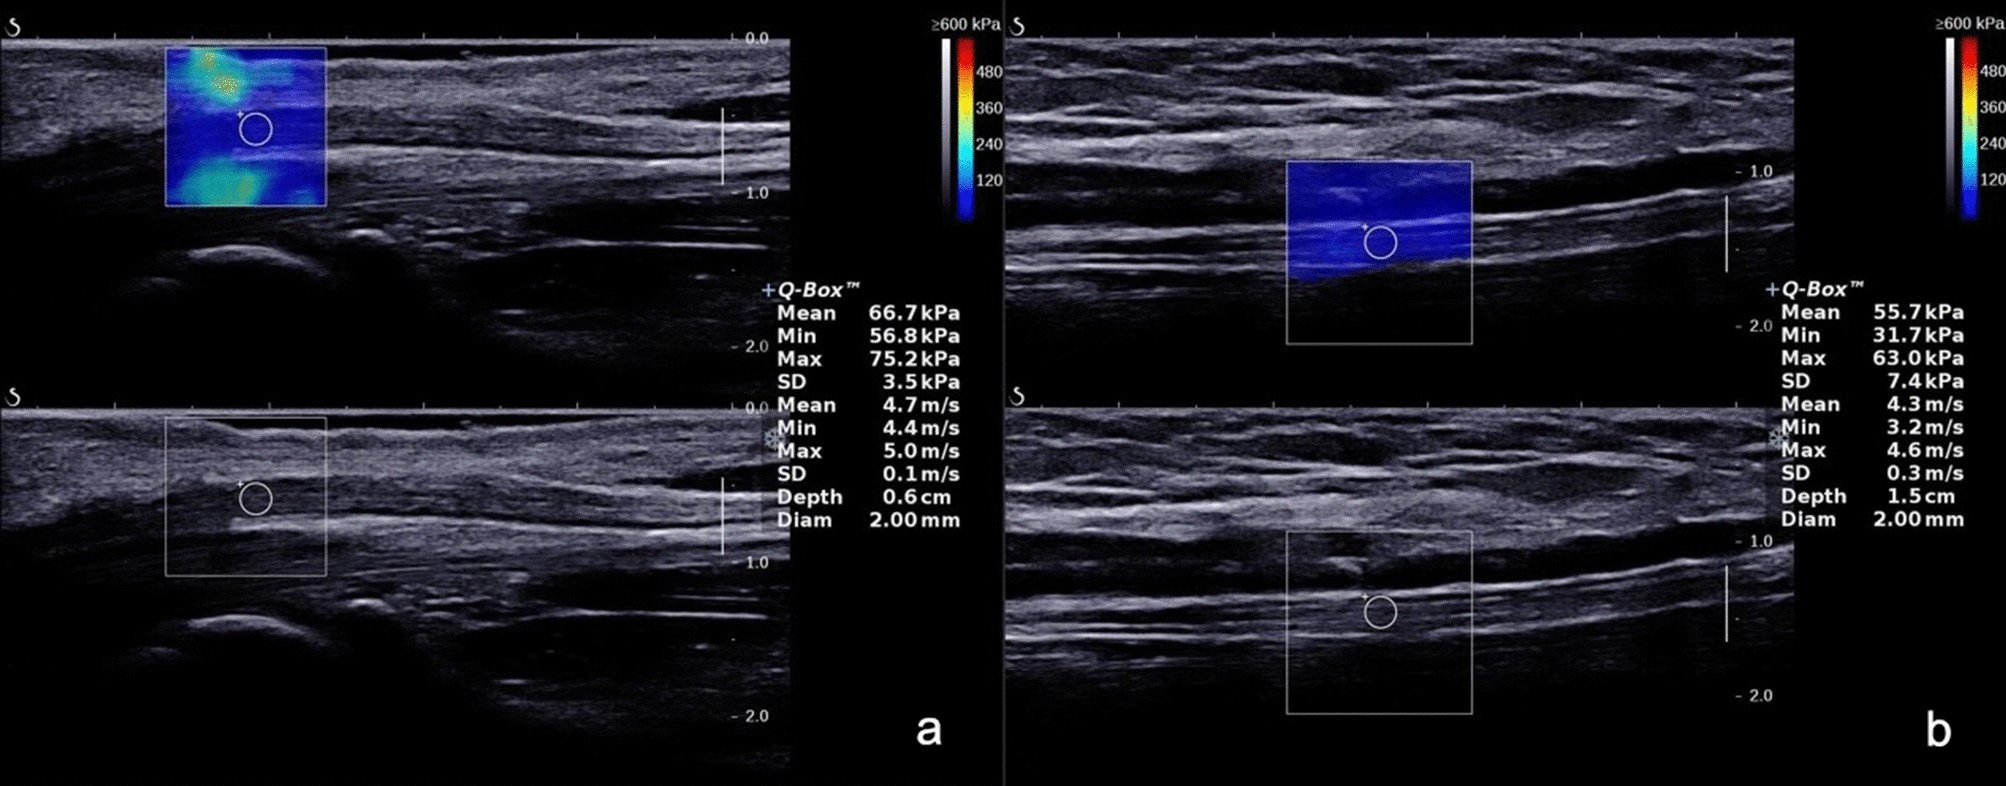

In the relaxed position, the shear wave velocity of the median nerve at the carpal tunnel (a) and the tibial nerve at the tarsal tunnel (b).